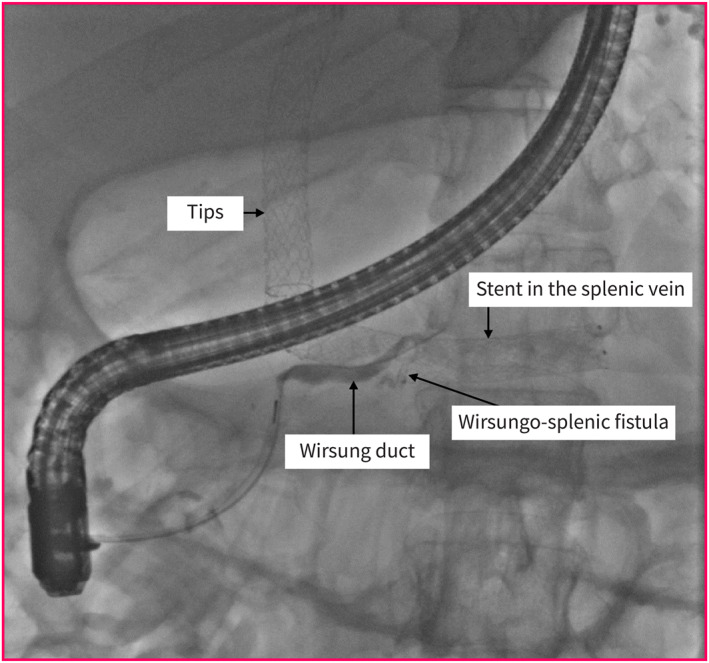

Pancreatic Panniculitis Without Pancreatopathy: A Rare Complication of Splenic Vein Stenting for Portal Hypertension in Myeloproliferative Syndrome.

无胰腺病变的胰膜炎:骨髓增生综合征门静脉高压脾静脉支架置入术中一种罕见的并发症。